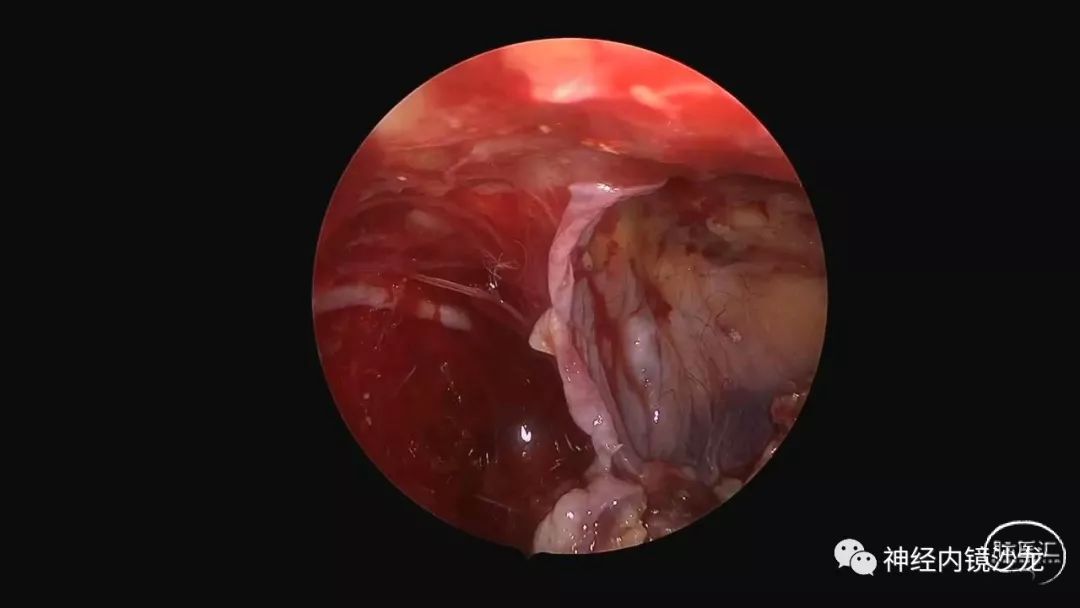

精彩图表

从事神经外科十余年,擅长神经外科肿瘤诊治,尤其是神经内镜微创手术治疗垂体瘤、颅咽管瘤、脑膜瘤等颅底肿瘤